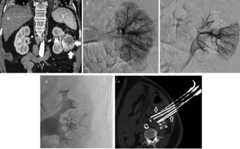

Over the last 2–3 years one of the main topics that has gained the attention of the interventional community concerns embolization therapy. The treatment of hemorrhoidal disease by transarterial embolization of the superior rectal arteries (SRA) (Figure1), and nicely presented by Vincent Vidal and his team in Marseille under the name of “emborrhoid technique” [4], was inspired by previous experiences reporting embolization as an alternative to surgery in urgent cases of massive bleeding [5]. Ligation of the terminal branches of the superior rectal artery, to reduce the arterial supply to the hemorrhoids, is already performed in routine surgical techniques, with more or less tissue resection: the Milligan and Morgan’s hemorrhoidectomy (resection of the three hemorrhoidal cushions); the Longo procedure (resection of a ring of a ring of rectal mucosa); the more recent Elective Doppler-guided hemorrhoidal artery ligation (DG-HAL) [6,7,8]. Hemorrhoidal disease is primarily managed by conservative treatment combining hygiene and dietary measures with phlebotonics, while surgical intervention is reserved to 10% of the patients [9]. The main issue remains a prompt recovery but the complication rate ranges from 2% to 20%, with various post-operative disadvantages such as hemorrhage, stenosis, anal incontinence, and abscess. Peritonitis due to rectal perforation has also been described [10,11,12,13]. Transarterial embolization proposes a mini-invasive selective approach to achieve targeted occlusion of the arterial in-flow without recurring to an invasive surgery that requires specific equipment such as an anoscope. The first publication of the early experience in three patients has been followed by a more recent report in 2016 reporting safety and efficacy of the technique in 40 subjects [14]. Particles and coils were used as embolization agents. Early results at one month demonstrated a significant regression of the emorrhoidal bundles, absence of ischemic risk, and normal sphincteric function recovered after one month. Hospitalization and recovery time were respectively 2.5 ± 0.5 days (with 75% of the patients discharged on the first day) and 6.2 ± 0.9 days. Further prospective trials are required to better define the role of the technique beside the surgical gold standards; concurrently, applications of the emborrhoid technique in particular urgent contexts of variceal bleeding and high-risk patients are showing up in the literature and deserve attention [15,16].

Figure 1.

A 20-year-old woman (medical student) with history of Cloves syndrome (venous malformation at the pelvis and left leg), presenting with life threatening perineal hemorrhage from hemorrhoidal bundles:(a) Selective arteriography of the inferior mesenteric artery (IMA, arrow) showing vascularization of the rectum by the superior rectal arteries (SRA, asterisks).(b) Focal hypervascularization corresponding to the hemorrhoids. Superselective embolization of the left trunk is performed using a coaxial microcatheter (c, arrow) and microcoils placement(d) with good angiographic and clinical results. The different distal branches, respectively left, right and posterior trunk can be embolized according to the angiographic findings and anatomical classifications.